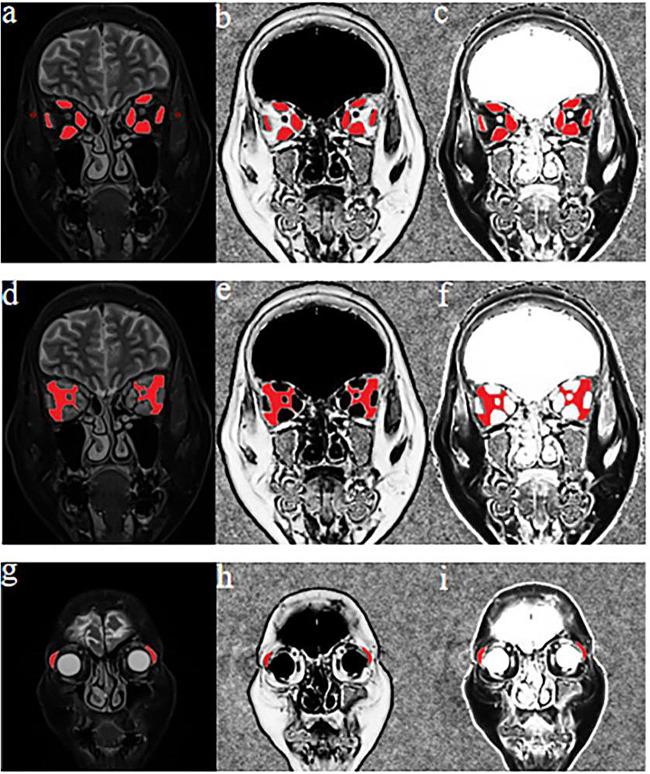

To investigate the value of Dixon magnetic resonance imaging (MRI)-based quantitative parameters of extraocular muscles (EOMs), intraorbital fat (IF), and lacrimal glands (LGs) in staging patients with thyroid-associated ophthalmopathy (TAO).

Two hundred patients with TAO (211 active and 189 inactive eyes) who underwent Dixon MRI for pretreatment evaluation were retrospectively enrolled and divided into training (169 active and 151 inactive eyes) and validation (42 active and 38 inactive eyes) cohorts. The maximum, mean, and minimum values of the signal intensity ratio (SIR), fat fraction (FF), and water fraction (WF) of EOMs, IF, and LGs were measured and compared between the active and inactive groups in the training cohort. Binary logistic regression analysis, receiver operating characteristic curve analysis, and the Delong test were used for further statistical analyses, as appropriate.

Compared with inactive TAOs, active TAOs demonstrated significantly greater EOM-SIR, EOM-SIR, EOM-SIR, IF-SIR, IF-SIR, LG-SIR, LG-SIR, EOM-WF, EOM-WF, IF-WF, IF-WF, and LG-WF and lower EOM-FF, EOM-FF, IF-FF, IF-FF, and LG-FF values (all p < 0.05). The EOM-SIR, LG-SIR, and LG-FF values were independently associated with active TAO (all p < 0.05). The combination of the EOM-SIR, LG-SIR, and LG-FF values showed better performance than the EOM-SIR value alone in staging TAO in both the training (AUC, 0.820 vs 0.793; p = 0.016) and validation (AUC, 0.751 vs 0.733, p = 0.341) cohorts.

Dixon MRI-based parameters of EOMs, LGs, and IF are useful for differentiating active from inactive TAO. The integration of multiple parameters can further improve staging performance.